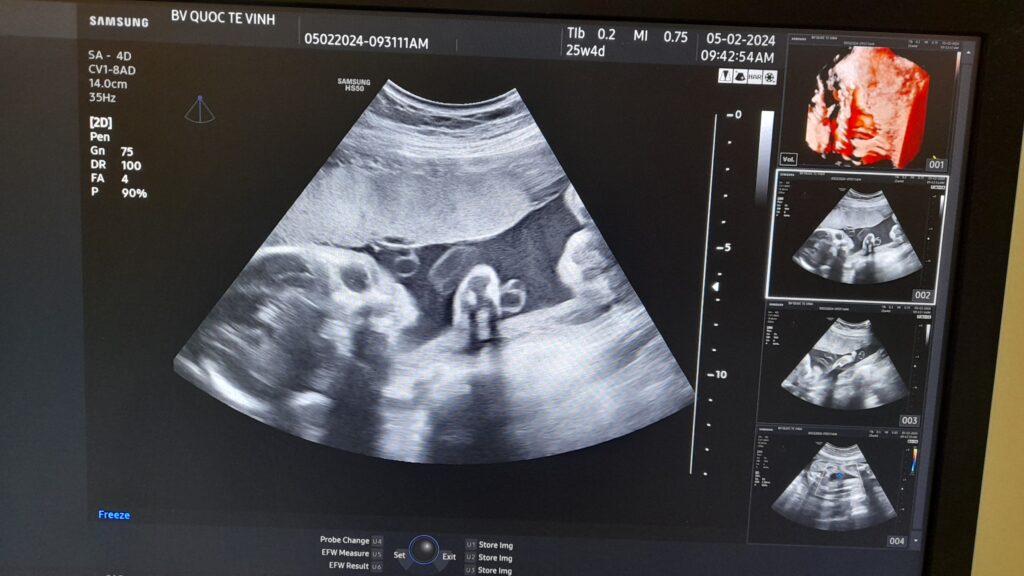

Một trường hợp siêu âm thai phát hiện dây rốn một động mạch tại Bệnh viện Hoàn Mỹ Vinh

Đây là một trường hợp thai phụ đến Bệnh viện Hoàn Mỹ Vinh để khám và sàng lọc dị tật thai nhi bằng siêu âm 4D. Trong quá trình siêu âm phát hiện thấy dây rốn của bé có 2 mạch máu, một tĩnh mạch, một động mạch. Thai nhi đã được bác sĩ kiểm tra kĩ để phát hiện các dị tật kèm theo, may mắn là em bé chỉ bị dây rốn một động mạch đơn độc, cân nặng và các chỉ số đều trong giới hạn tăng trưởng bình thường theo ISOUGH, tiên lượng tốt. Bác sĩ đã giải thích cho thai phụ, tư vấn và hướng dẫn thai phụ khám thai định kỳ để theo dõi sự phát triển của bé.